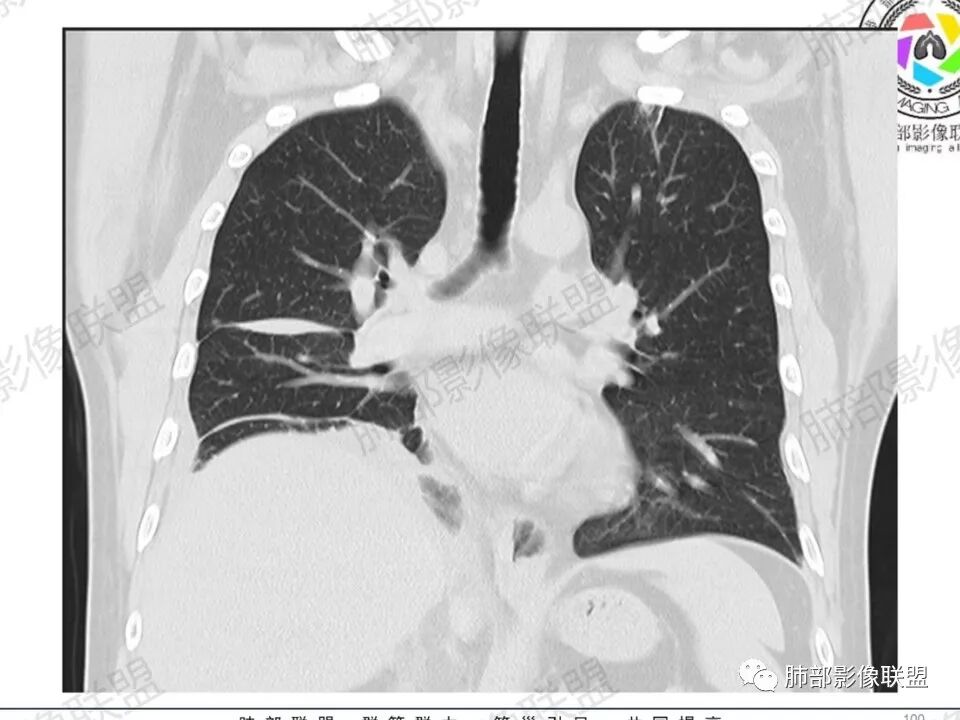

双肺多发结节,胸膜下为主,部分可见空洞。左肺上叶尖后段结节较大,分叶毛刺,周围可见长条索及小斑片影,内空洞比较光滑,内侧壁可见支气管通过。右肺下叶后基底段不张实变,后侧积液,右侧水平裂积液,右侧膈胸膜纵膈胸膜增厚积液,右侧侧胸膜肥厚,考虑1:一元金葡。2二元:金葡,左肺上叶结核。

感觉还是金葡入血形成SPE可能性较大,胸水+楔形影+胸膜结节

中年男性,左手中指及胸壁疼痛伴发热来诊,影像见双肺多发结节,胸膜下分布为主,部分结节可见空洞,边缘模糊。左肺上叶尖后段结节较大。右肺下叶后基底段不张实变,右侧叶间裂及右侧胸腔积液,右侧侧胸膜肥厚。考虑金葡菌感染,血播SPE。

胸膜下为主多发结节,边缘光滑

伴随楔形影,支气管壁不增厚